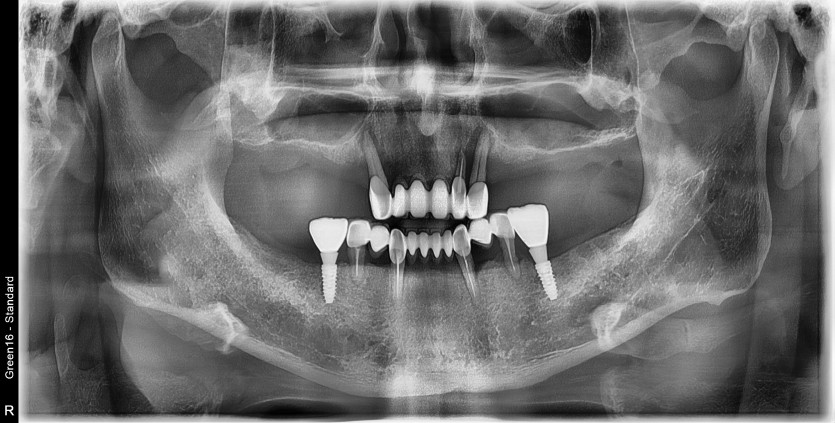

만 58세 전체 임플란트 증례

전체 임플란트 증례입니다.

16개의 임플란트로 완성하였습니다.